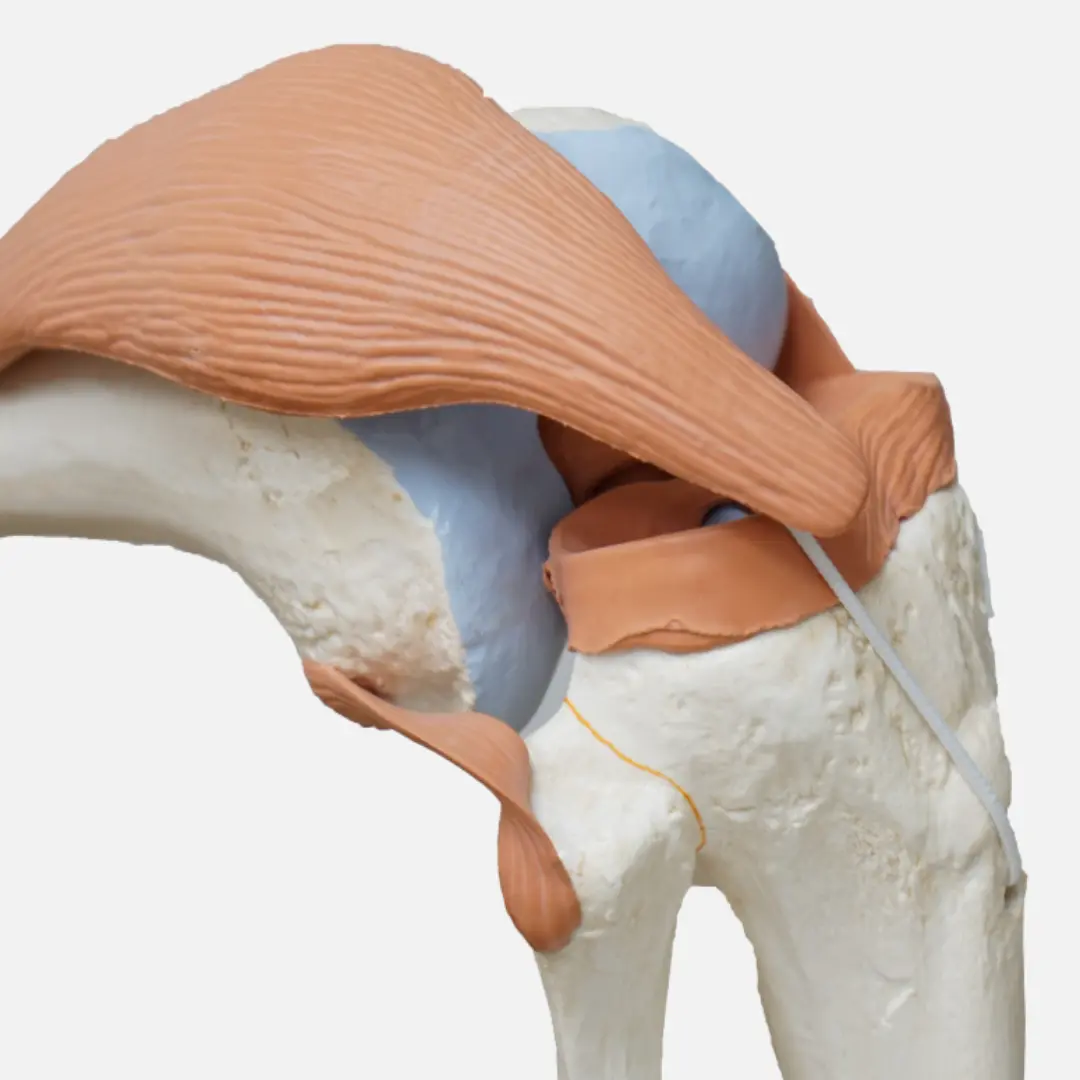

글루코사민(Glucosamine)은 우리 몸에서 자연적으로 생성되는 아미노당의 일종이에요. 주로 연골, 인대, 힘줄, 피부 등 결합 조직에 풍부하게 존재하며, 특히 관절 연골의 주요 구성 성분인 프로테오글리칸(Proteoglycan)과 히알루론산(Hyaluronic acid)의 중요한 재료가 됩니다.

연골은 관절에서 뼈와 뼈가 직접 부딪히는 것을 막아주고, 충격을 흡수하며, 부드러운 움직임을 가능하게 하는 쿠션 역할을 합니다. 이 연골은 콘드로이틴과 함께 글루코사민을 통해 건강하게 유지될 수 있어요. 하지만 나이가 들거나, 과체중, 과도한 운동 등으로 인해 연골이 손상되거나 글루코사민 생성 능력이 떨어지면 연골이 닳아 없어지고 탄력을 잃게 됩니다. 이는 결국 관절 통증과 염증을 유발하는 퇴행성 관절염으로 이어질 수 있어요.

- 연골 보호 및 재생 촉진:

- 글루코사민은 연골의 주요 구성 성분인 프로테오글리칸과 히알루론산의 생성을 돕는 핵심 물질입니다. 손상되거나 닳아 없어지는 연골의 구성 성분을 보충하고, 연골 세포의 재생을 촉진하는 데 기여할 수 있어요.

- 연골이 튼튼해지면 관절이 받는 충격을 효과적으로 흡수하고, 뼈와 뼈 사이의 마찰을 줄여 통증을 예방할 수 있습니다.